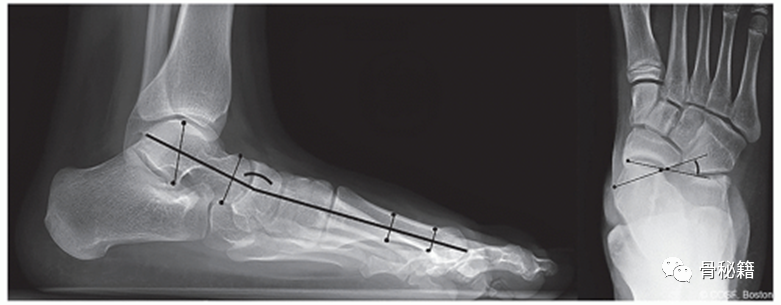

站立 AP 和足部侧位 X 光片对于评估畸形的严重程度和相关足部状况是必要的。应评估侧位 X 线片上的尾骨角和跟骨俯仰角,以及在 AP 视图上的距舟覆盖作为存在相关)。拇外翻畸形及其严重程度的表征基于测量结果HVA 评估第一跖骨干和近节指骨纵轴之间的角度。该角度应小于 15°。IMA 是第一和第二跖骨干之间的角度,是跖骨内翻程度的量度,应小于 9°。远端跖骨关节角 (DMAA) 测量第一跖骨远端关节面相对于其长轴的方向,通常小于 10°。还应评估跖趾关节的一致性。由于跖骨内翻,大多数青少年拇囊炎的 IMA 增加,DMAA 增加和跖趾 (MTP) 关节一致。

显示外侧距第一跖骨(Meary)角和前后距舟覆盖角测量值的 X 光片。

照片显示 (1) HVA、(2) IMA 和 (3) DMAA 的测量值。

DMAA,远端跖骨关节角;HVA,拇外翻角;IMA,跖骨间角。

术前计划 (AP) 足部 X 光片,

说明跖骨截骨的位置(白线)、计划的矫正(弯曲箭头)和预期的最终结果。